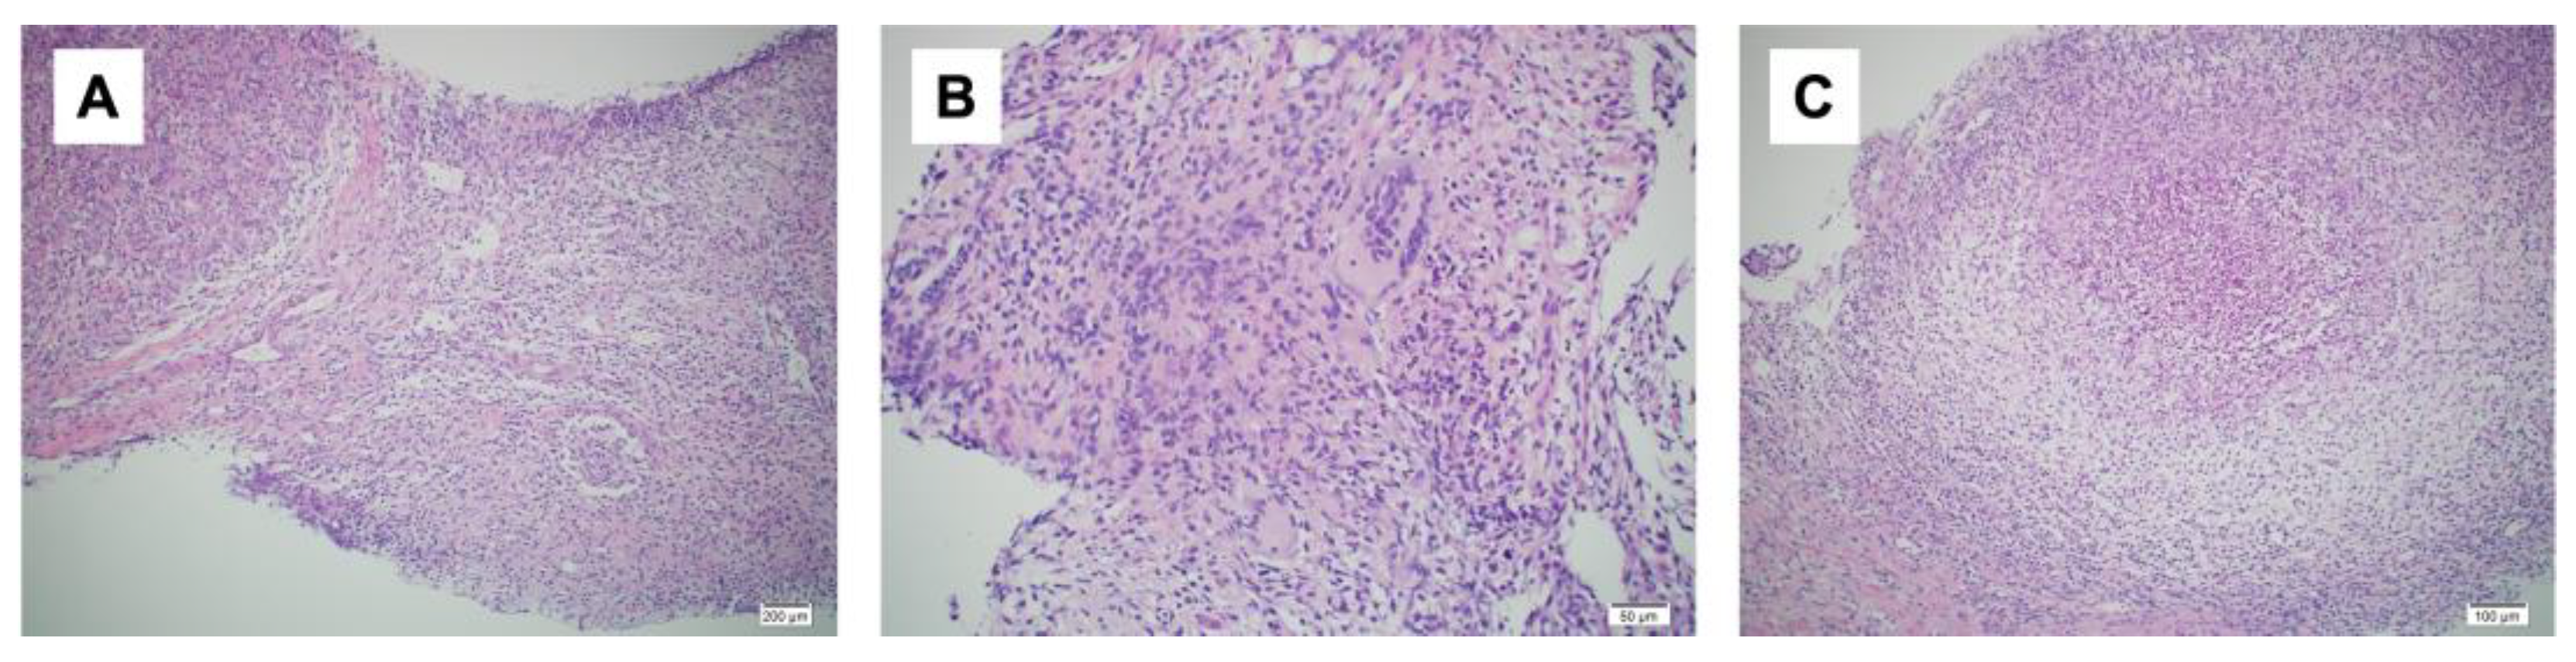

A day after the elective cesarean section, a bacterial culture and needle biopsy of the left mammary gland were performed. The bacterial culture results again revealed the presence of C. kroppenstedtii. The needle biopsy revealed granulomatous mastitis (Figure 3A–C). Based on these examination results, the patient was diagnosed with granulomatous mastitis. One month after surgery, the patient’s symptoms flared up again, and she was started on prednisolone 20 mg/day after weaning. Two weeks after starting prednisolone, the dose was reduced to 10 mg/day and the wound healed with iodine ointment. Prednisolone was gradually decreased, the treatment was terminated four weeks after the initial treatment had begun, and the patient was examined during follow up checkups. However, one week later, her symptoms re-emerged and prednisolone was started again at 30 mg/day. The symptoms improved, prednisolone tapered off, and the patient recovered completely after two months. One and a half years after the surgery, no recurrence was observed.

Figure 3.

Histopathological findings. (A): Non-dysbutyroid epithelial granuloma (hematoxylin-eosin [HE] staining ×10); (B): area consisting of a cluster of multinucleated giant cells (hematoxylin-eosin [HE] staining ×20); (C): area of an abscess (hematoxylin-eosin [HE] staining ×10).